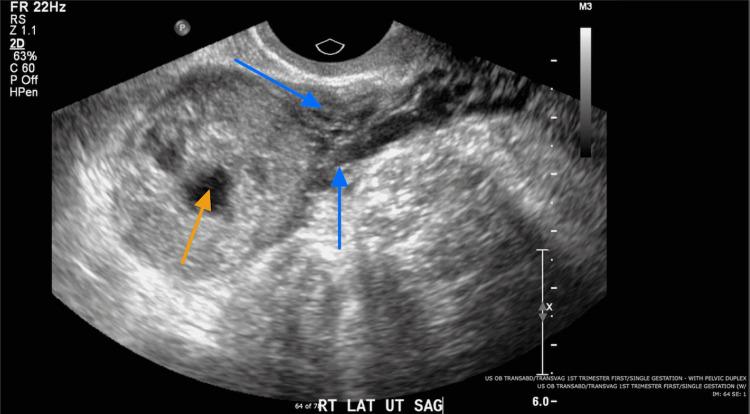

β-hCG超过39,000 mIU/mL的间质部妊娠的保守治疗:一例报告

Interstitial ectopic pregnancy can be a life-threatening condition as the myometrial tissue around the gestational sac is thin. Furthermore, the interstitial aspect of the fallopian tubes is highly vascularized. Thus, a rupture in this area can result in catastrophic hemorrhage, hemoperitoneum, and shock. Therefore, surgical management is often the preferred mode of therapy. This report identifies the successful medical management of a patient with interstitial ectopic pregnancy with β-hCG of more than 39,000 utilizing methotrexate.

间质部异位妊娠可能是一种危及生命的情况,因为妊娠囊周围的子宫肌层组织很薄。此外,输卵管间质部血管高度丰富。因此,该区域的破裂可导致灾难性出血、腹腔积血和休克。所以,手术治疗通常是首选的治疗方式。本报告确定了一名间质部异位妊娠患者,其β - 人绒毛膜促性腺激素超过39000,使用甲氨蝶呤进行药物治疗成功的案例。